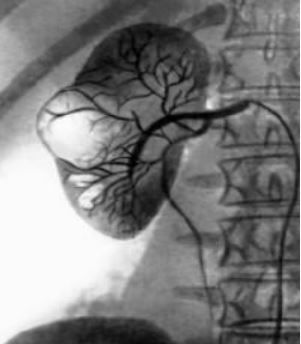

Почечная киста — полостное образование в ткани почки, имеющее капсулу и заполненное жидкостью. Данное заболевание встречается и у мужчин, и у женщин с одинаковой частотой, чаще диагностируется у пациентов в возрасте после 40 лет.

Кисты почек могут быть единичными и множественными (мультикистоз). Бессимптомное течение кисты не требует хирургического вмешательства. При наличии показаний производится лапароскопическое иссечение кисты.